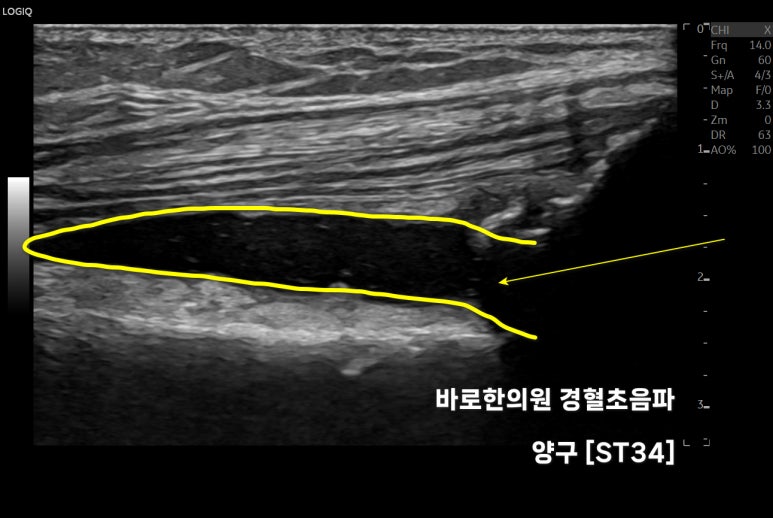

위 영상은

제가 출판한

초음파 전공서적인데요.

대퇴직근의 긴장을 치료하는

핵심 혈자리,

의

표준 초음파 영상입니다.

문제가 있는 혈자리를

손으로 찾은 뒤

최대 효과를 내는 깊이로

초음파 약침을 시술합니다.

근육을 싸고 있는 막을

한 겹 한 겹 떼어내면서

정확한 깊이로 시술합니다.

시술 후 영상을 보면

근막을 따라 약침이 들어간 것을

알 수 있습니다.